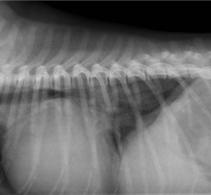

Durante la realización de las radiografías torácicas (Fig. 3), el paciente sufrió una pérdida de consciencia, rigidez y cambio de coloración de las mucosas (cianosis). En la auscultación, los ruidos cardíacos se encontraban disminuidos y el pulso femoral se notaba más débil y rápido respecto a lo observado en la exploración física previa al examen ecocardiográfico. Debido al estado inestable del paciente se optó por iniciar un

tratamiento de soporte sin la realización de otras pruebas complementarias. Se comenzó el tratamiento de soporte con oxigenoterapia y fluidoterapia basada en cristaloides calculada como un bolo de 2 ml/kg administrado en 15 minutos, monitorización del electrocardiograma donde se observó la presencia de taquicardia sinusal a 185 latidos por minuto, y medición de la presión arterial de forma no invasiva, con valores de presión sistólica de 85 mmHg compatibles con hipotensión.

Posteriormente se evaluó al paciente mediante un examen TFAST, detectando derrame pericárdico y disminución del tamaño del AI (Fig. 4), como hallazgos diferentes a los observados en el examen realizado previo a la radiografía. La rápida respuesta por parte del equipo veterinario implicó que en este primer examen ecográfico tras el desvanecimiento del paciente no se había producido la formación del coágulo para taponar la fisura de la pared, observando flujo desde el AI hacia el saco pericárdico. Se realizaron exámenes TFAST seriados para evaluar la necesidad de realizar una pericardiocentesis al paciente durante la hora si-

Figura 1. Corte paraesternal derecho 4 cámaras, previo a la rotura del atrio izquierdo. VI: ventrículo izquierdo; VD: ventrículo derecho; AI: atrio izquierdo; AD: atrio derecho. Figura 2. Corte paraesternal derecho transversal a la altura del atrio izquierdo y aorta, previo a la rotura del atrio izquierdo. Ao: aorta; AI: atrio izquierdo. Figura 3. Radiografía torácica latero-lateral derecha realizada en el momento que se produjo la rotura del atrio izquierdo. Figura 4. Examen TFAST tras la rotura del atrio izquierdo donde podemos observar un corte transversal del corazón a la altura de los músculos papilares de ventrículo izquierdo. Se puede observar la presencia de derrame pericárdico. VD: ventrículo derecho; VI: ventrículo izquierdo.

guiente al episodio. En los exámenes seriados realizados no se observaron signos ecocardiográficos de taponamiento cardíaco, por lo que se decidió no realizar un vaciado del contenido pericárdico mediante pericardiocentesis9,10 y se optó por un tratamiento de soporte basado en oxigenoterapia y fluidoterapia, buscando mantener un correcto gasto cardíaco sin aumentar en exceso la presión sistólica del paciente, lo que podría producir un aumento del sangrado a través del defecto de la pared atrial, así como una dosis única de pimobendán (Vetmedin, Boehringer Ingelheim, Rhein) por vía intravenosa a 0,15 mg/kg. A los 15 minutos tras el episodio de desvanecimiento, se observó la presencia de una estructura hiperecoica en la pared del AI en el examen ecográfico, compatible con la formación de un coágulo (Fig. 5).

Figura 5. Corte paraesternal derecho 4 cámaras tras la rotura del atrio izquierdo. Se puede observar la formación de una estructura compatible con un coágulo dentro del saco pericárdico. AD: atrio derecho; AI: atrio izquierdo.